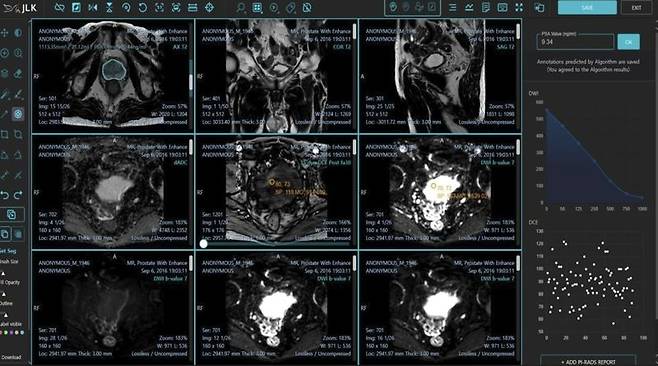

의료 인공지능(AI) 1호 상장기업 제이엘케이는 자사가 개발한 AI 전립선암 진단 솔루션 'MEDIHUB Prostate'가 미국 식품의약국(FDA) 510(k) 승인을 획득했다고 24일 발표했다.

[파이낸셜뉴스] 의료 인공지능(AI) 1호 상장기업 제이엘케이는 자사가 개발한 AI 전립선암 진단 솔루션 ‘MEDIHUB Prostate’가 미국 식품의약국(FDA) 510(k) 승인을 획득했다고 24일 발표했다.

이번 FDA에서 승인된 MEDIHUB Prostate는 제이엘케이가 서울아산병원, 미국 미주리대학과의 임상시험으로 개발한 전립선암 진단 AI 솔루션이다. 전립선암의 진단과 추적에는 다중 매개변수(Multiparametric) 전립선 MR 영상이 활용되며, 질병에 대한 조직학적 이해 및 MR 영상에 대한 많은 경험이 필요하다.

또 판독의사들의 숙련도에 따라 진단의 난이도가 있는 질환으로 세계적으로 인증된 바이오 마커인 PIRADS (Prostate Imaging Reporting and Data System) 점수를 표준화해 사용하고 있다.